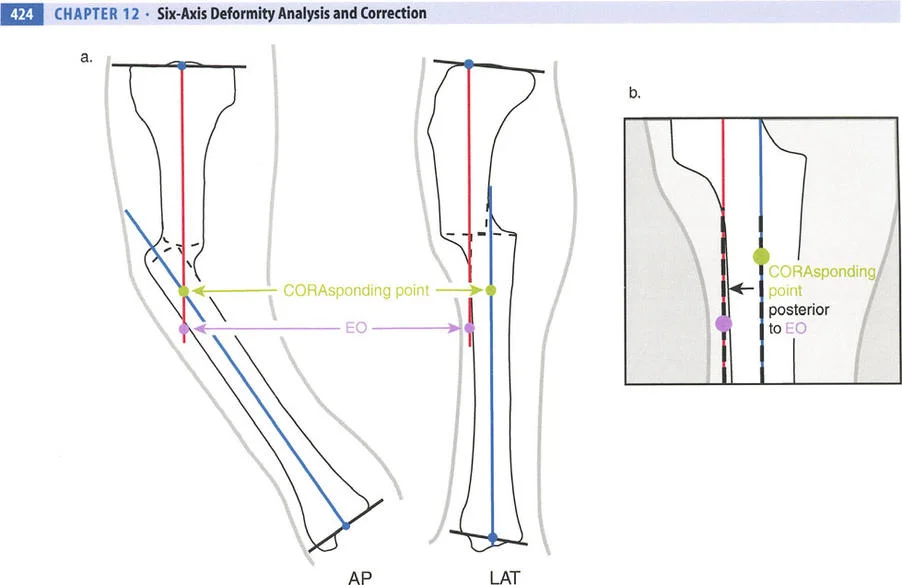

- الأشعة السينية الطويلة للطرفين (Long-leg Standing X-rays): هذه الأشعة ضرورية لتقييم المحور الميكانيكي للطرف بالكامل أثناء الوقوف. تسمح بتحديد مركز دوران الانحراف (CORA) بدقة، وهو النقطة التي يجب أن تتمحور حولها عملية التصحيح.

تحدي مركز دوران الانحراف (CORA) القريب من المفصل

لمطابقة مفصلة المثبت الخارجي مع المستوى الدقيق لمركز دوران الانحراف (CORA)، يجب غالبًا بناء المفصلة فوق أو تحت مستوى الحلقة الفعلية. يُعرف هذا في مبادئ بالي باسم تجميع المفصلة القريبة من المفصل (juxta-articular hinge assembly).

إذا كان مركز دوران الانحراف (CORA) يقع بالقرب من خط المفصل، فإن وضع حلقة إليزاروف القياسية عند هذا المستوى بالضبط مستحيل دون انتهاك مساحة المفصل أو شد الهياكل الكبسولية الحيوية. لذلك، يتم تثبيت الحلقة المرجعية بالعظم الكثيف أو العظم الطويل المتاح، ويتم بناء آلية المفصلة باستخدام قضبان ملولبة، ولوحات توصيل، ودعامات. ثم يتم "إنزالها" (أو رفعها) لتتطابق تمامًا مع مركز دوران الانحراف (CORA) الهندسي الحقيقي.

- قاعدة قطع العظم 1: عندما يمر قطع العظم ومحور تصحيح الانحراف (ACA) كلاهما عبر مركز دوران الانحراف (CORA)، فإن نهايات العظم ستنحرف دون ترجمة (انزياح). يتم استعادة المحور الميكانيكي، وتظل نهايات العظم متقاربة تمامًا، مما يخلق تصحيحًا كلاسيكيًا "إسفينيًا مفتوحًا" أو "إسفينيًا مغلقًا".

- قاعدة قطع العظم 2: عندما يمر محور تصحيح الانحراف (ACA) عبر مركز دوران الانحراف (CORA)، ولكن يتم إجراء قطع العظم على مستوى مختلف (غالبًا بسبب ضعف جودة العظم عند CORA أو مشاكل في الجلد)، فإن نهايات العظم ستنحرف وتخضع لترجمة محسوبة ومقصودة لإعادة محاذاة المحور الميكانيكي.

- قاعدة قطع العظم 3: (للاكمال) عندما يمر قطع العظم عبر مركز دوران الانحراف (CORA)، ولكن يتم وضع محور تصحيح الانحراف (ACA) خارج CORA، سيتم إنشاء تشوه ترجمة جديد، وهو خطأ شائع في وضع المفصلات غير المخطط له جيدًا.

في المنشآت القريبة من المفصل، غالبًا ما نعتمد على قاعدة قطع العظم 2. نظرًا لأنه لا يمكننا قطع العظم بأمان عند خط المفصل تمامًا (مركز دوران الانحراف CORA)، فإننا نقطع العظم في مستوى أدنى في منطقة الميتافيسيس. بعد تحقيق التصحيح الزاوي عبر المفصلات (محور تصحيح الانحراف ACA)، يتم إعادة محاذاة خطوط المحور الميكانيكي بشكل مثالي، ولكن نهايات العظم في موقع قطع العظم تتحرك بالنسبة لبعضها البعض.